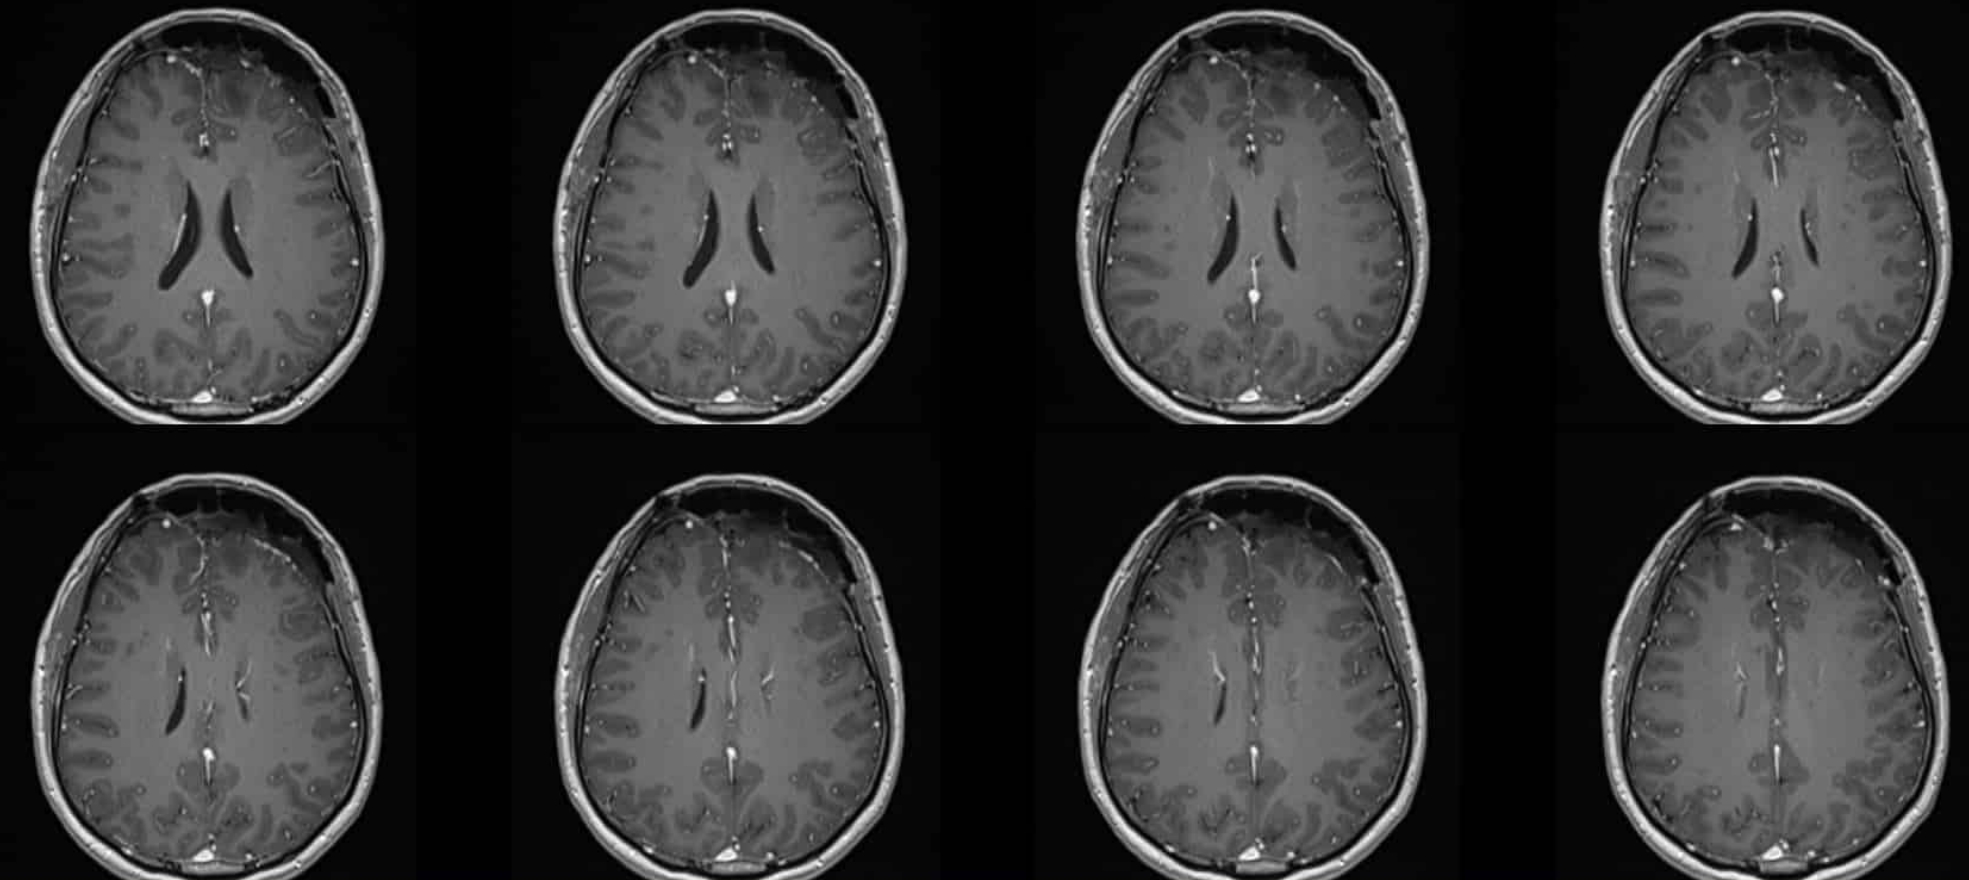

MRI

術后頭顱MR:腫瘤全切